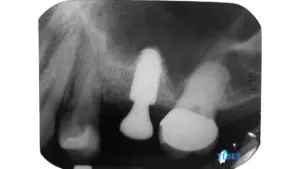

這種治療結果不是天天都看得到,很多時候得要靠運氣以及醫師的經驗。乍看兩張根管治療重新治療前後的X光片,一般患者大概看不出什麼差別,即使是牙醫師有時候也得改變拍攝角度去嘗試自己辛苦努力的成果。